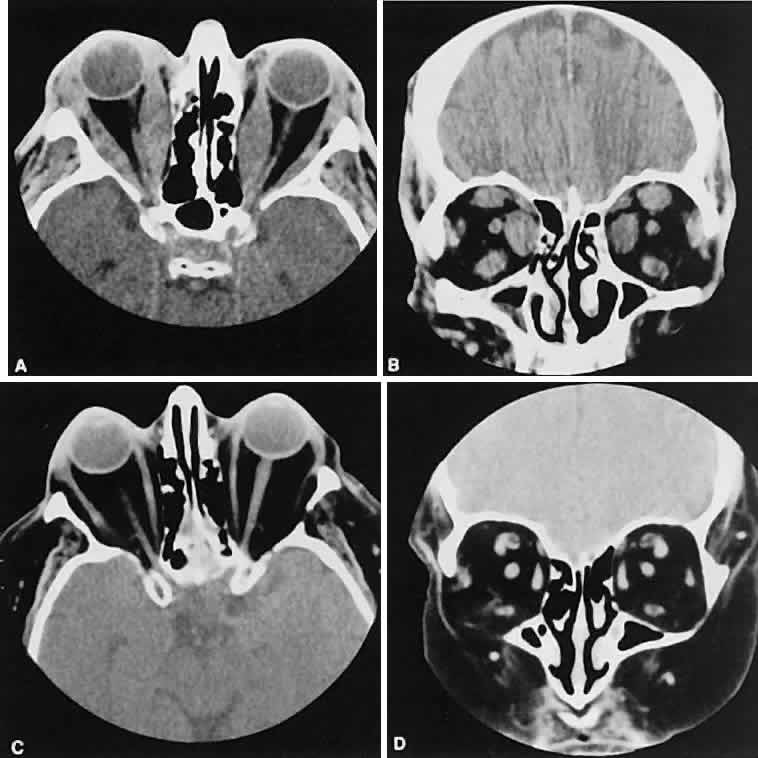

Graves' orbitopathy probably represents the most frequent cause of proptosis and EOM enlargement. The CT findings are fairly stereotyped and typically display various degrees of EOM enlargement (Fig. 7). The inferior rectus muscle usually is affected earliest, followed by the medial rectus, superior rectus, and finally the lateral rectus muscle. Rootman and colleagues13 noted more frequent involvement of the superior rectus/levator and medial rectus muscles than what had been reported previously with Graves' orbitopathy. These muscles can be affected in isolation, with the exception of the lateral rectus. To the best of our knowledge, isolated lateral rectus enlargement has not been reported in Graves' orbitopathy and in our experience usually is associated with a sphenoid wing meningioma.

Fig. 7. Graves' orbitopathy with two variations. Axial (A) and coronal (B) views show symmetric fusiform enlargement of the extraocular muscles with tapered muscle insertions. Note the predominant enlargement of the inferior, medial, and superior rectus muscles with lesser involvement of the lateral rectus muscle, a frequent pattern of enlargement in Graves' orbitopathy. Axial (C) and coronal (D) views of Graves' orbitopathy with expansion of retrobulbar ground substance and relative sparing of the extraocular muscles.

CT evidence of Graves' orbitopathy tends to be bilateral. Approximately 86% of patients with unilateral clinical findings have bilateral CT findings in our experience, which is consistent with the experience of others.42

Morphologically, the EOM belly is enlarged, with a gradual tapering toward and sparing of the tendinous portion of the muscle. Tendon involvement is a typical feature of orbital myositis. Tendon involvement helps to differentiate this lesion from Graves' orbitopathy, although Rootman and Nugent43 have noted a rare patient with Graves' orbitopathy with this finding.